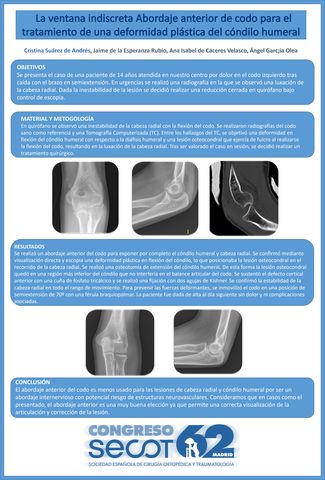

La ventana indiscreta: Abordaje anterior de codo para el tratamiento de una deformidad plástica del cóndilo humeral

CRISTINA SUAREZ DE ANDRES, JAIME DE LA ESPERANZA RUBIO, ANA ISABEL DE CÁCERES VELASCO, ANGEL GARCIA OLEA